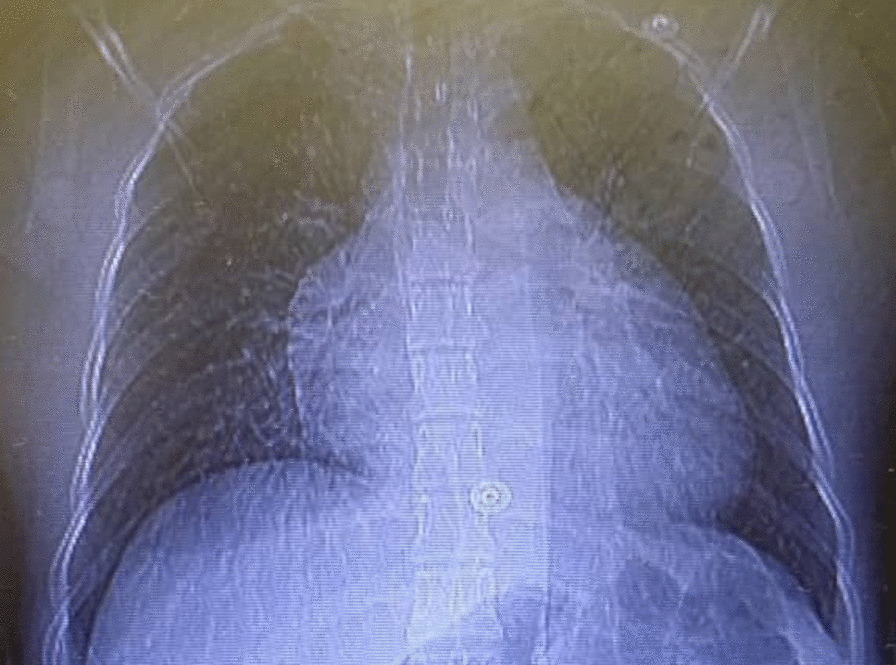

On the eighth day of second admission, she again developed severe dyspnea and pulmonary edema, and her blood pressure was 110/70, heart rate 110 beats per minute, respiratory rate 25 breaths per minute, and audible crackles in the lower third of both lungs. Intravenous furosemide 40 mg stat and 6 mg per hour started, which stabilized her condition. Echocardiography was performed again on the 11th day of admission, showing LVEF of 30%, global hypokinesis, LV enlargement (LV end diastolic size 5.8 cm), and normal right ventricle (RV) size with reduced RV systolic function. Again, IVIG 20 g/day was started and continued for 3 days. On the 12th day of admission, the patient’s clinical status stabilized and her symptoms disappeared. Chest X-ray showed improvement of lung infection and no evidence of pulmonary edema (Fig. 3). Her heart rate decreased to 70 beats per minute with a respiratory rate of 14 breaths per minute. Oxygen saturation on room air was 95%, and her body temperature was 37.0 °C (by mouth).

Fig. 3.

Chest X-ray showing improved COVID-19 infection and no pulmonary edema with cardiomegaly on 12th day of admission